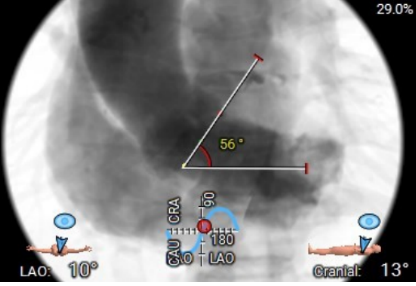

右窦居中位:LAO:9° CAU:11°

主动脉瓣环夹角:56°

患者为老年女性,冠脉搭桥术后,二次外科开胸风险极高,为保证手术安全,邀请心外科支持,做好手术应急预案。CT提示主动脉瓣二叶式type1型,L-R融合,瓣叶增厚、黏连,瓣叶游离缘、根部及融合脊中-重度钙化;主动脉瓣狭窄严重,瓣口面积小,需耐心跨瓣。计划采用22mm球囊预扩张,根据球囊扩张情况,可以选择22mm/25mm的杰成主动脉瓣膜,植入瓣膜后根据瓣膜形态及血流动力学参数决定是否进行后扩张。患者颈动脉存在狭窄,术中起搏时的低血压状态有可能造成脑供血不足,增加脑梗风险,术中预扩时应迅速,减少低血压时间,杰成瓣膜释放时无需快速起搏,常规血压状态下即可快速释放,极大的缩短了起搏和低血压时间。另外该例患者外周血管纤细,股动脉直径仅5.7mm,考虑采用18F血管鞘,并注意外周血管保护,尽力避免血管并发症。